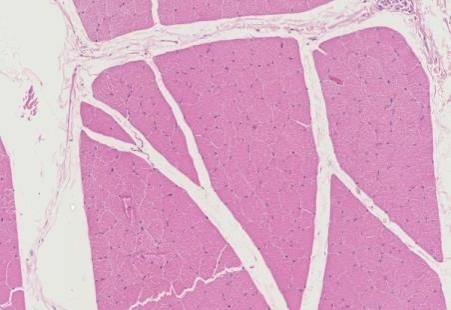

Yes, the lesions depend on the stage of the disease. In the acute phase the muscle is grossly swollen and histologically shows multifocal and variable amounts of inflammatory cells, including lymphocytes, macrophages, plasma cells and sometimes eosinophils (this is why in some texts the disease was also known as eosinophilic myositis) (figures 1 and 2). Fibrosis is not usually observed at this stage.

In chronic stages of disease there is extensive interstitial fibrosis and atrophy of many muscle fibres (figure 3). Regeneration features of muscular fibers can be present. Our animal is unfortunately probably at the chronic stage of the disease, since there is already severe atrophy of masticatory muscles